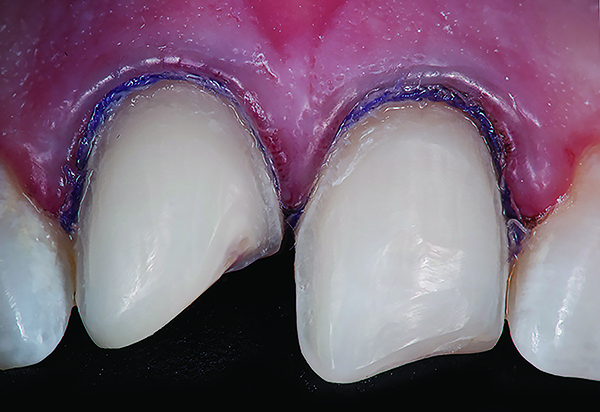

Figure 1 Preoperative, preparation, and final postoperative images of a 2-unit CL-I feldspathic veneer case.

Figure 1

Figure 2 Preoperative, preparation, and final postoperative images of a 2-unit CL-I feldspathic veneer case.

Figure 2

Figure 3 Preoperative, preparation, and final postoperative images of a 2-unit CL-I feldspathic veneer case.

Figure 3

CL-I materials are fabricated by hand (Figure 4); they are the most conservative and generally the most translucent ceramic materials, but they are also the weakest.9,10,18 The material’s high translucency and esthetics create the illusion of natural teeth.9 Powder/liquid porcelain materials are ideal for cases in which significant enamel remains and/or there is healthy tooth structure on the teeth (ie, 50% or more remaining enamel on the tooth, 50% or more of the bonded substrate is enamel, and 70% or more of the margin is in the enamel). Feldspathic porcelain restorations that are bonded to primarily enamel substrates have proven to be highly successful long term.19

Powder/liquid porcelains demonstrate high esthetics and workability, and because they can be layered very thinly and placed directly on the enamel, they are considered the most conservative of the metal-free ceramic classes.10 CL-I porcelains require a thickness of 0.2 mm to 0.3 mm for each shade change.20,21

This class of materials is generally indicated for anterior restorations, but can also be used for the occasional bicuspid and rare molar, providing all parameters are at a very low risk level (Figure 5 and Figure 6).